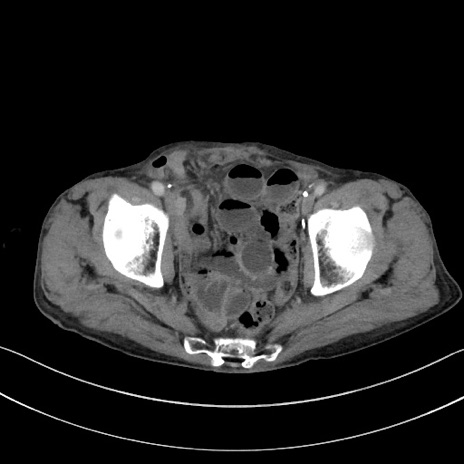

症例3(横断像)

【症例】 70歳代男性

【主訴】右鼠径部腫瘤、疼痛

【現病歴】本日朝より上記主訴あり、受診。

【既往歴】膀胱癌にて膀胱全摘、両側尿管皮膚瘻

【データ】WBC 5600、CRP 0.56